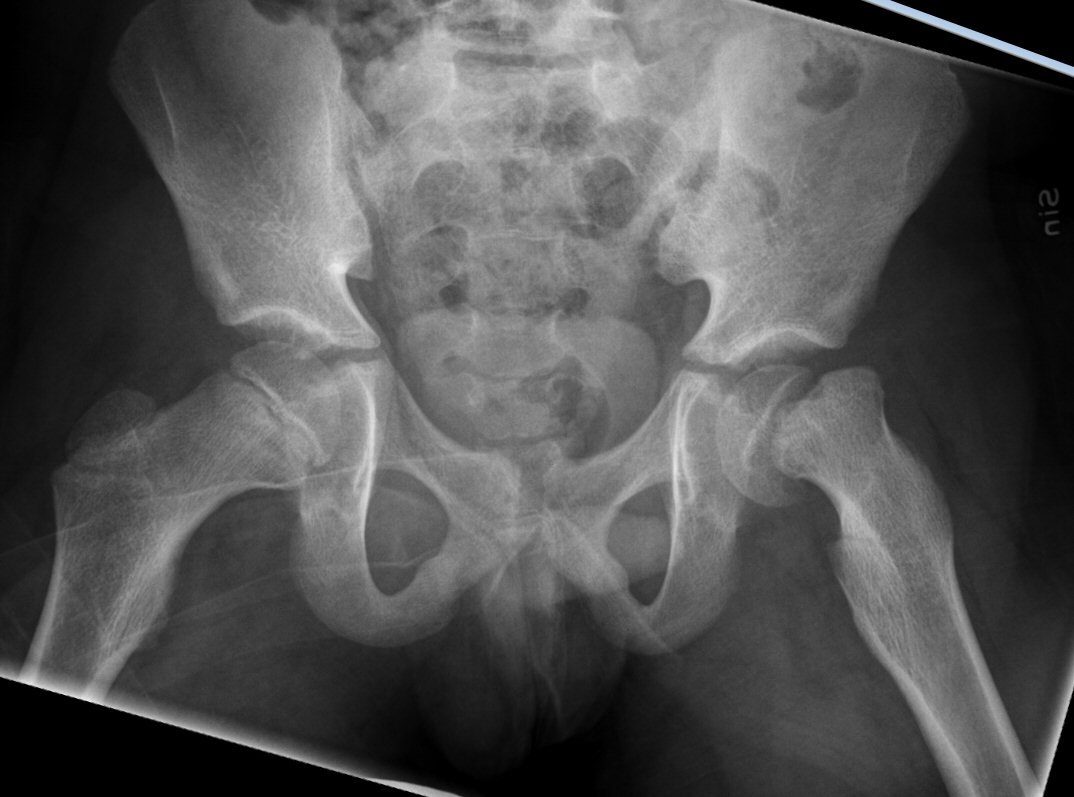

- Slätröntgen [1] av bäcken i "Lauensteinprojektion" (grodläge) och båda höfterna.

- Kleins linje - en linje längs med kollums laterala sida på frontalvy - ska gå genom kaput.

Fysiolys vänster höft akut, efter primär operation resp. innan spikextraktion efter 6 år

- Vid misstanke: akut röntgenundersökning [1] av bäcken i "Lauensteinprojektion" (grodläge) och båda höfterna.